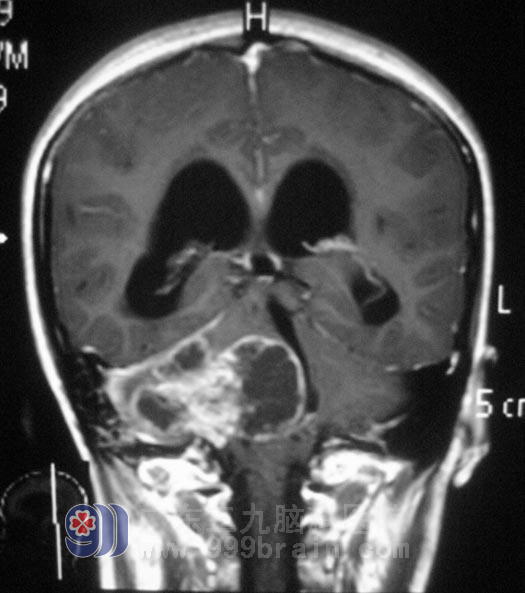

二十岁的小何,两个月前因右耳听力下降伴头痛、头晕,检查发现右侧桥小脑角区囊实性占位,直径约4.5cm,伴幕上梗阻性脑积水,在当地医院行右侧桥小脑角区肿瘤切除手术,术后肿瘤残留。小何一直存在右耳听力障碍,头痛、头晕症状逐渐加重。二周前她开始出现间断呕吐,走路不稳,双眼视力下降。这是一次不是很满意的手术治疗。

2月23日,由综合神经外科 鲁明主任主刀,在全麻下行右侧桥小脑角区残留肿瘤切除术,术中取原切开入路,显微镜下见肿瘤位于右侧桥小脑角,呈黄白色,周围纤维组织增生明显。显微镜下分块切除,术中电生理检测,右侧听神经形态菲薄,面神经位于肿瘤前下方,舌咽神经、迷走神经位于肿瘤后下方,与肿瘤粘连紧密,细心分离完整保留,残留肿瘤全切,手术顺利结束。术后经过治疗,小何未出现吞咽困难、构音障碍、面瘫等症状,可以自行行走,已满意出院。术后病理结果:神经鞘瘤。